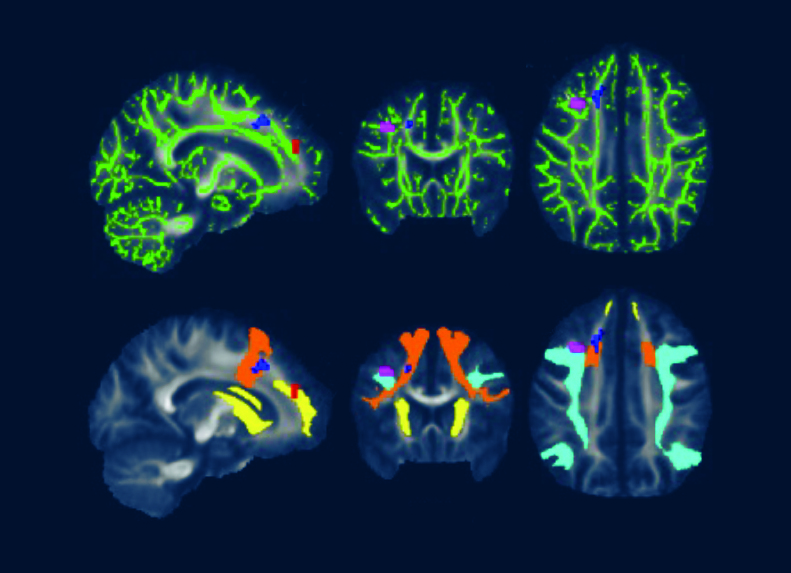

A 2022 Johns Hopkins University School of Medicine neuroimaging study utilized fMRI and DTI brain scans in conjunction with each other. These scans identified striking functional abnormalities as well as distinct structural changes in the white brain matter of Lyme disease patients.[iv]

Cherie Marvel, PhD, lead author of the fMRI/DTI study and Associate Professor, Departments of Neurology & Psychiatry at Johns Hopkins University School of Medicine, describes fMRI as “a quantitative ‘brain stress test’ that measures brain function during cognitive tasks.”

Dr. Marvel explains that “the brain scans indicate Lyme disease patients’ brains work harder than normal and unexpectedly by activating white matter in the frontal lobe to try to maintain normal function.”

DTI, a measure of structural brain integrity, confirms abnormalities in the same white matter regions as observed in the fMRI scans.

Caption for featured photo: DTI brain images from a 2022 Johns Hopkins University School of Medicine study show white matter changes associated with post treatment Lyme disease.